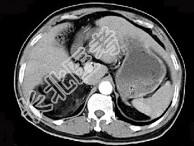

- 单项选择题男,59岁, 右侧腰背酸痛,CT检查如图所示, 应诊断为 ( )

A、右肾上腺腺瘤

B、右肾上腺转移瘤

C、右肾上腺髓样脂肪瘤

D、右腹膜后脂肪瘤

E、右肾血管平滑肌脂肪瘤